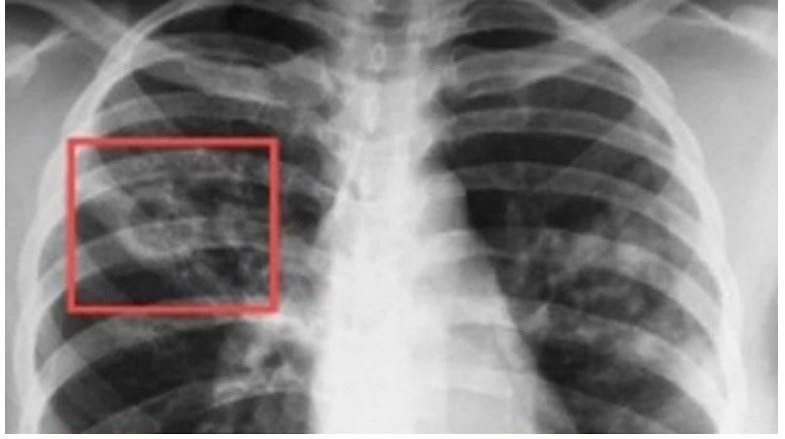

Учените откриха начин да забележат рака на белия дроб още преди първите симптоми

Учени от Бостънския университет в САЩ откриха начин да научат за наличието на рак на белия дроб преди първите симптоми на заболяването.

Те успяха да открият геномни различия в нормалната тъкан на дихателните пътища, които са свързани с работата на имунната система и могат да бъдат открити преди началото на предраковата активност в човешкото тяло, съобщава MedicalXpress.